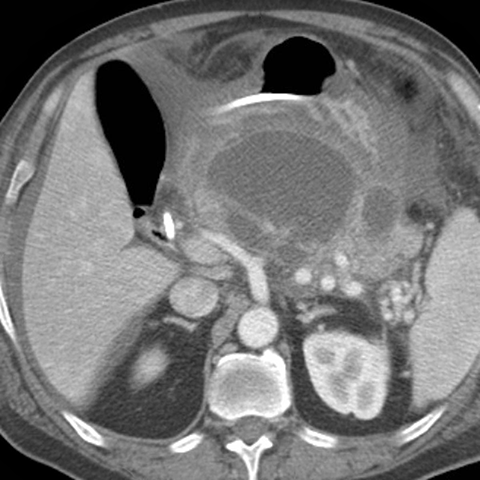

Pancreatic Pseudocyst [2 of 3]